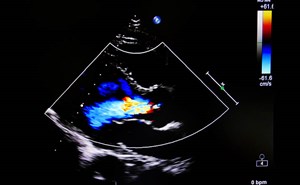

Acute Mitral Regurgitation in the Emergency Department

A 56-year-old female with history of hyperlipidemia, mild mitral regurgitation, and type 2 diabetes presents to the emergency department for 5 days of diffuse chest pain with dyspnea, lower extremity ...